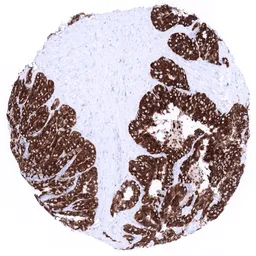

IHC-P analysis of human colorectal adenocarcinoma (COAD) tissue using GTX04409 Mucin 6 antibody [MSVA-806R] HistoMAX™.

Strong and diffuse mucin 6 immunostaining in a colorectal adenocarcinoma.